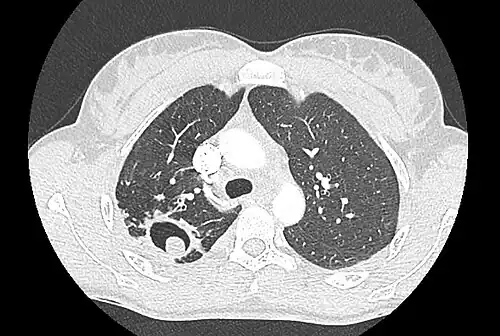

Sur la radiographie pulmonaire, un aspergillome simple apparaît comme un nodule dense, le plus souvent entouré d'un croissant aérique[11]. La radiographie seule ne suffit pas au diagnostic ; un scanner est recommandé[29]. Sur le scanner thoracique, le centre de la cavité est occupé par l'aspergillome[58]. La pseudo-tumeur bouge dans la cavité lorsque le patient change de position (signe de Monod)[58]. Dans l'aspergillome simple, il n'y a pas d'évolution entre les examens et la paroi de la cavité est le plus souvent fine[13]. Un aspergillome complexe[13] présente en revanche l'aspect d'une cavité (ou plusieurs) à parois épaisses, comportant en son centre une truffe aspergillaire. Il existe parfois un début de fibrose pulmonaire[59]. La plèvre adjacente a également un aspect fibrosé, et l'évolution radiologique est lente, mais toujours vers l'aggravation[13]. Un halo en verre dépoli peut également entourer les lésions[45].

- Le changement de position modifie la position du grelot aspergillaire dans la cavité (signe de Monod).